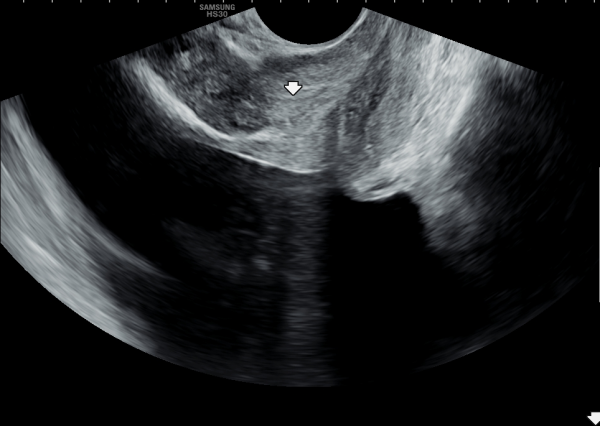

상급 의료 기관에서 회음부 통증과 배뇨장애등의 증상이 치료 되지 않아 내원 당일 경직장 전립선 초음파 검사상 사정관입구의 순환 장애로 사정관 낭종이 관찰되는 경직장 전립선 초음피 사진입니다.

This is a transrectal prostate ultrasound image taken on the day of the patient’s first visit, following persistent perineal pain and urinary symptoms that were not resolved at a tertiary care hospital. The image shows a seminal duct (ejaculatory duct) cyst caused by circulatory obstruction at the duct opening.

주 2~3회 가량 전립선의 표적 치료후 사정관 낭종이 치료 되었으나 사정관 주위에 탈락된 상피 세포의 관리가 필요한 추적 경직장 전립선 초음파 사진입니다.

This is a follow-up transrectal prostate ultrasound image taken after receiving targeted prostate therapy 2 to 3 times per week. The ejaculatory duct cyst has been resolved, but there is a need for continued management of the exfoliated epithelial cells around the ejaculatory ducts.